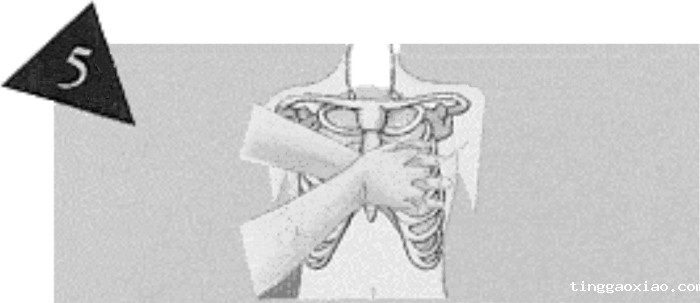

正确的胸外按压位置:

由病人的胸部(近施救者侧),找寻肋骨下缘,沿肋骨缘向上滑动,至肋骨与胸骨交汇的胸窝处,即为按压位置。

将中指置于心窝处,食指紧靠中指,置于胸骨上定位。

将另一掌的掌根紧靠在已定位的食指旁,使掌根的位置正好放在胸骨的中线上。

掌根放好位置后,另一手重叠于其上。

将两手的手指互扣或跷起,以免压迫肋骨造成骨折。